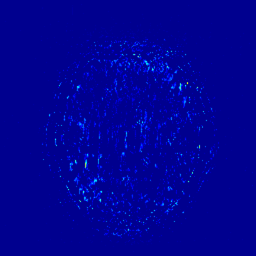

We illustrate with reconstructions for three CS-MRI methods: TLMRI (transform learning MRI) [25], PANO (patch-based nonlocal operator) [23] and GBRWT (graph-based redundant wavelet transform) [14]. The PANO and GBRWT models achieve impressive reconstruction qualities because they use an nonlocal prior and adaptive graph-based wavelet transform to exploit image structures. In TLMRI, the sparsifying transform learning and the reconstruction are performed simultaneously in more efficient way than DLMRI [24]. The three methods represent the state-of-the-art performance in the non-deep CS-MRI models. In Figure 2, we show the reconstructions error for zero-filled (itself a potential reconstruction “algorithm”), TLMRI, PANO and GBRWT on a complexed-valued brain MRI using 30%percent3030\% Cartesian under-sampling. The error display ranges from 0 to 0.2 with normalized data. The parameter setting will be elaborated in the Experiment Section V.

We also consider the deep learning DC-CNN model [26] as the guide module. We also give the reconstruction error in Figure 2. We observe the zero-filled, TLMRI, PANO, GBRWT and DC-CNN models all suffer the structural reconstruction errors, while the DC-CNN model achieves the highest reconstruction quality with minimal errors because of its powerful model capacity. Another advantage of this CNN model is that, once the network is trained, testing is very fast compared with conventional sparse-regularization CS-MRI models. This is because no iterative algorithm needs to be run for optimization during testing since the operations are a simple feed forward function of the input. We compare the reconstruction time of TLMRI, PANO, GBRWT and DC-CNN for testing for Figure 2 in Table I.

Figure 2: The reconstruction error of a brain MRI using zero-filled, TLMRI, PANO, GBRWT and DC-CNN under 1D 30%percent3030\% under-sampling mask.